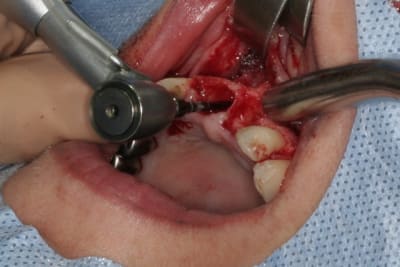

tien, ce matin, extraction de 24/25, curetage méticuleux, forage, comblement du gap, pose des 2 implants qui se sont bloqués à 50Ncm au CA sur les 3 ou 4 mm apicaux, pose des vis de cicat, sutures...35min....tranquille...

un autre cas EII MCI sur 11/21...mais en photos (j'ai aussi la vidéo, faut que je la passe sur youtube)